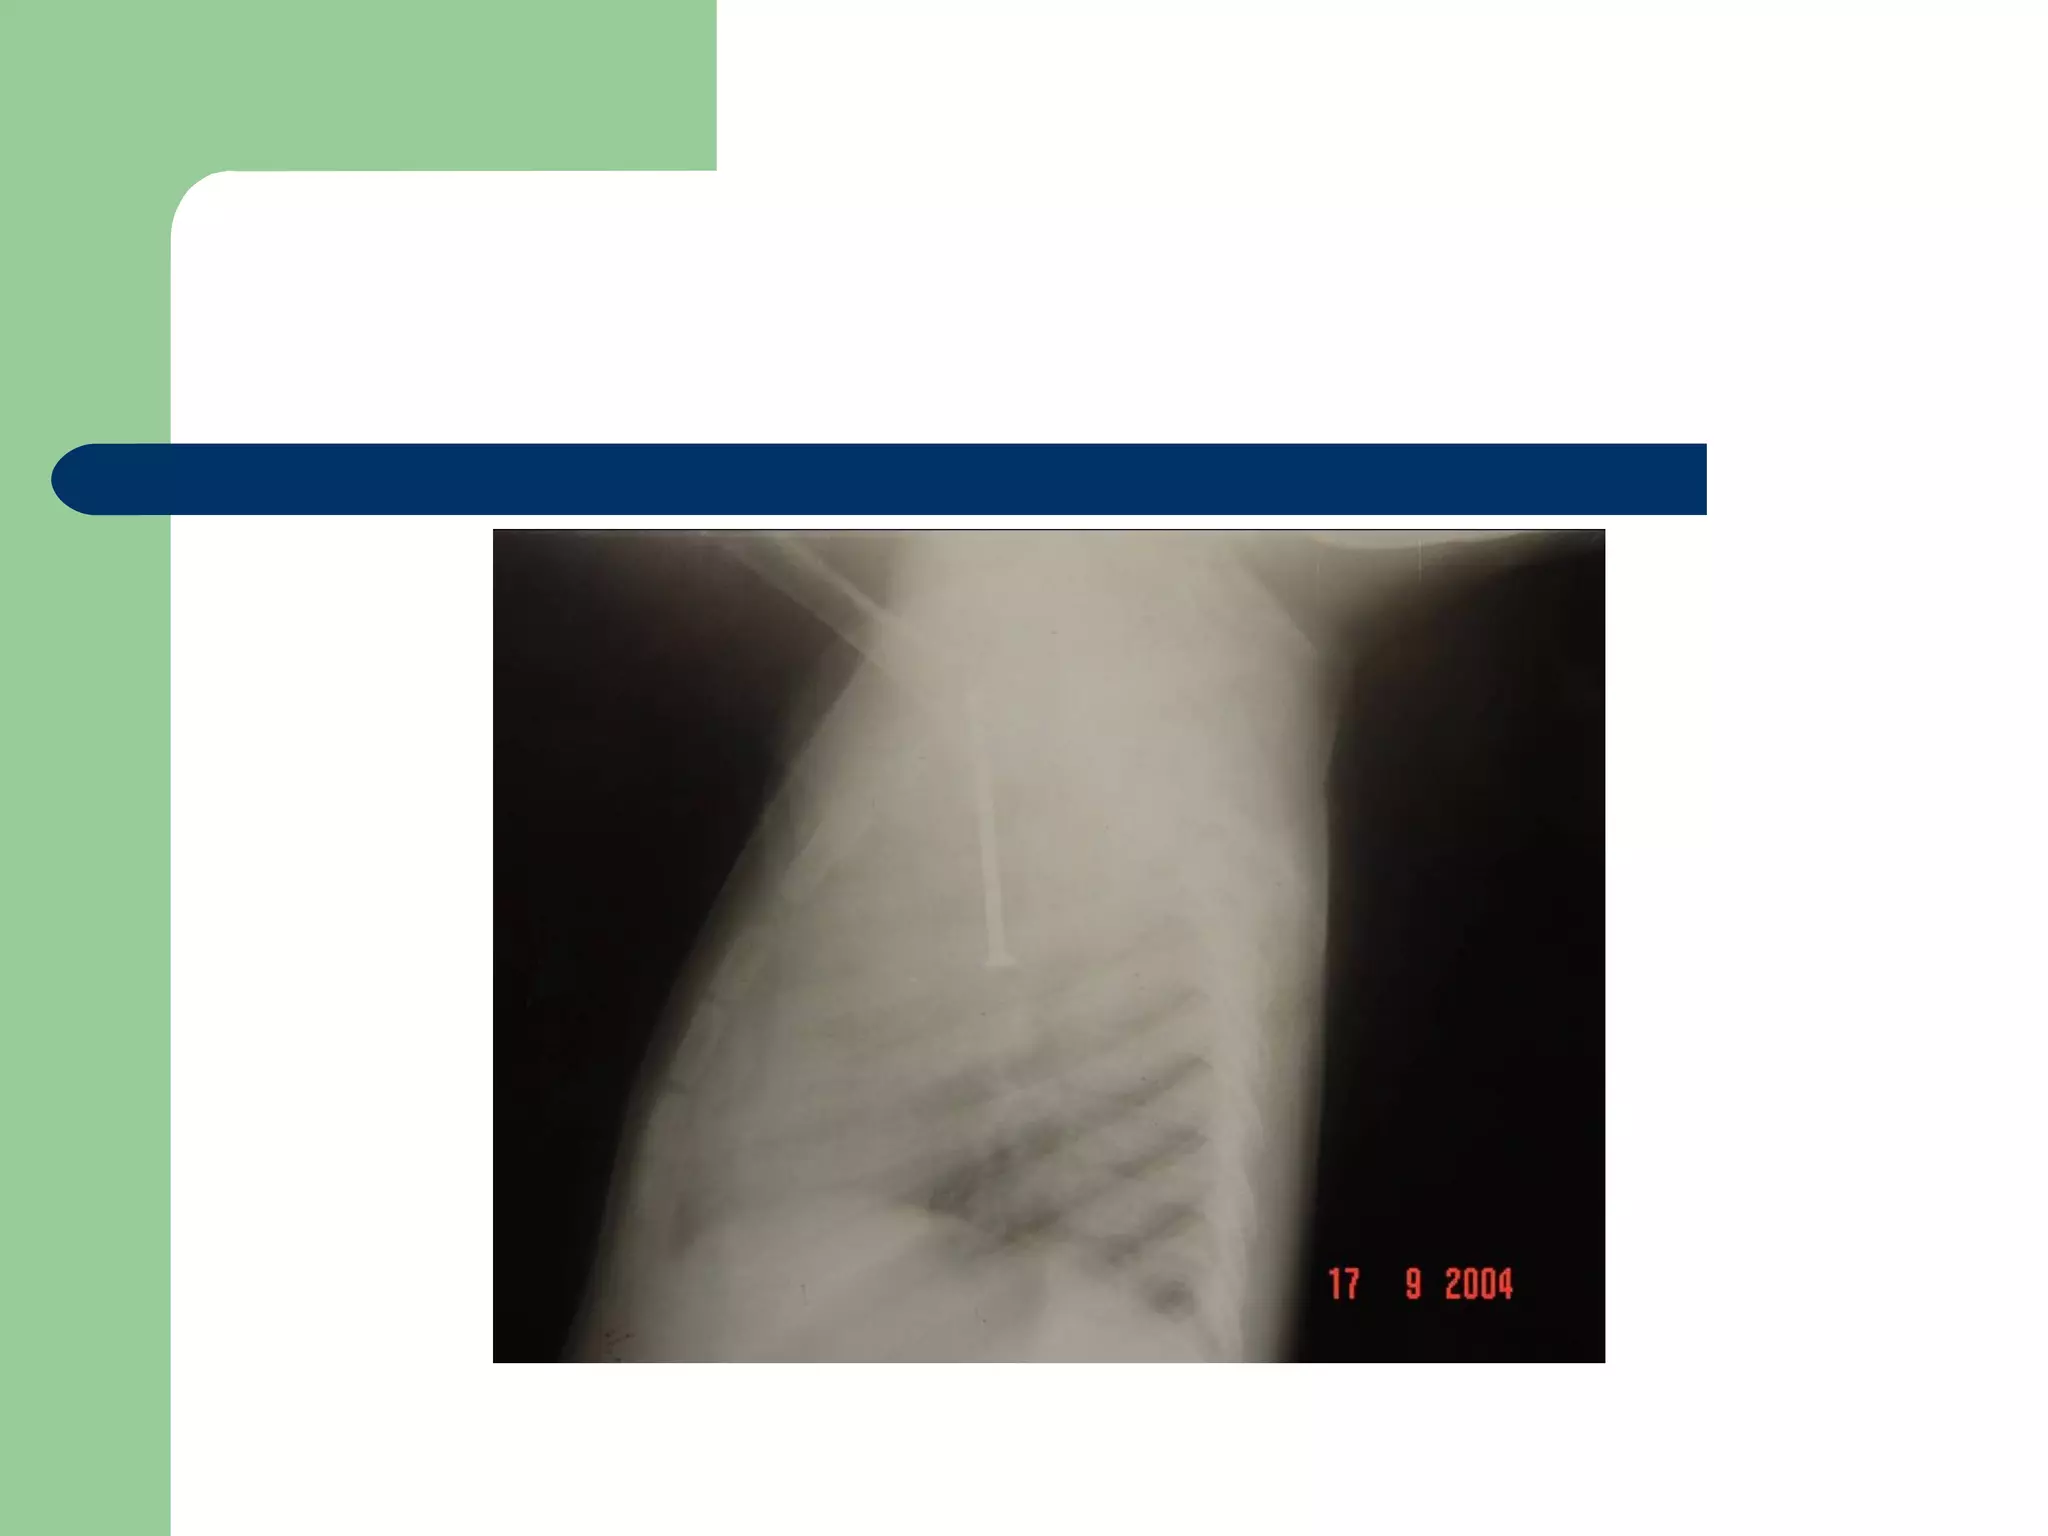

A five and a half yr old boy: non-resolved cough

Of 40 days duration

DIAGNOSIS…  Examination:signs of respiratory distress may be present.  CXR may be normal if the FB is not radio- opaque. or it can show a radio- opaque FB such as bone. Obstructive emphysema: is produced by intra-bronchial FB that allows air to enter in inspiration and prevents its exit in expiration. Lung collapse (complete or partial) is produced by a FB that blocks the bronchus completely. Unresolved pneumonic consolidation. Lung abscess or broncheictasis are caused by a long-standing FB.

A five anda half yr old boy: non-resolved cough Of 40 days duration